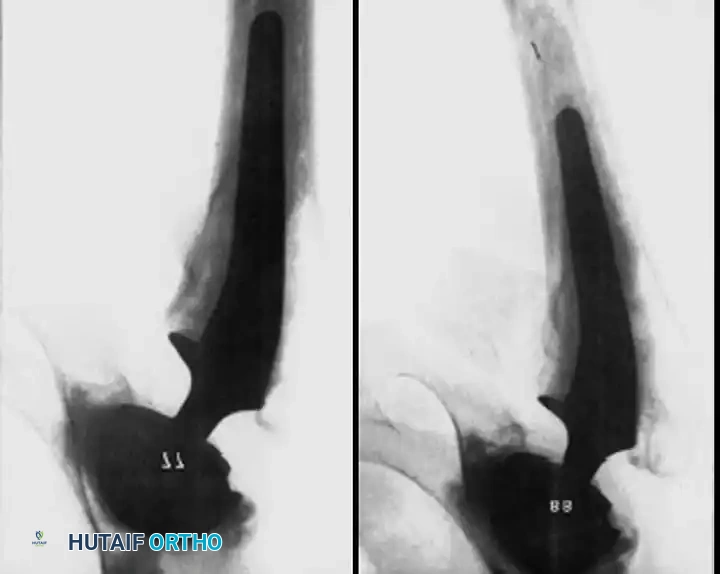

Associated Surgical & Radiographic Imaging